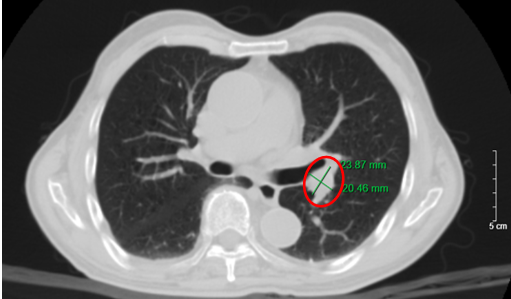

Hình 1. Hình ảnh nhu mô thùy trên phổi có nốt bờ không đều, tua gai, đường kính 26x17 mm (vòng tròn đỏ) trên phim chụp cắt lớp vi tính (cửa sổ trung thất).

Hình 2. Hình ảnh khối u bờ tua gai, đường kính 26x17 mm (vòng tròn đỏ), kèm hình ảnh dày tổ chức kẽ kèm các dải xẹp phổi nhu mô phổi trái. Giãn phế nang trung tâm lan tỏa rải rác nhu mô phổi, trên phim chụp cắt lớp vi tính (cửa sổ nhu mô).